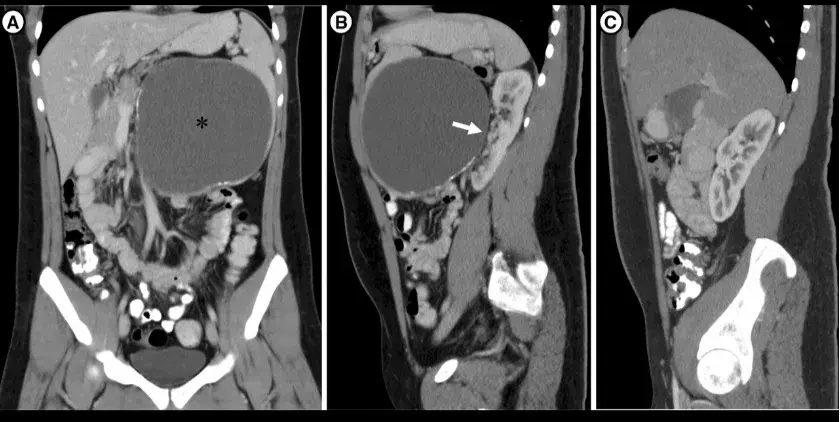

Após 04 após o último tratamento a paciente evoluiu com **novo** quadro de **edema nos membros inferiores**, **proteinúria** **de 8 g/dia** e **creatinina sérica de 1,27 mg/dl** (TFGe 37,5 ml/min/1,73m²), foi realizada uma nova biópsia renal (figura abaixo).

A microscopia de luz revelou glomérulos com lesões insudativas, hialinização arteriolar e proliferação mesangial (Figura 1A), mas **nenhuma** lesão ativa da nefrite lúpica foi identificada. A imunofluorescência mostrou **apenas** deposição linear de IgG ao longo da membrana basal glomerular com escassa deposição granular (Figura 1B). A microscopia eletrônica demonstrou apagamento do processo podocitário e espessamento da membrana basal.

Esses achados foram diagnósticos de **nefropatia diabética sobreposta a lesões crônicas de nefrite lúpica**.